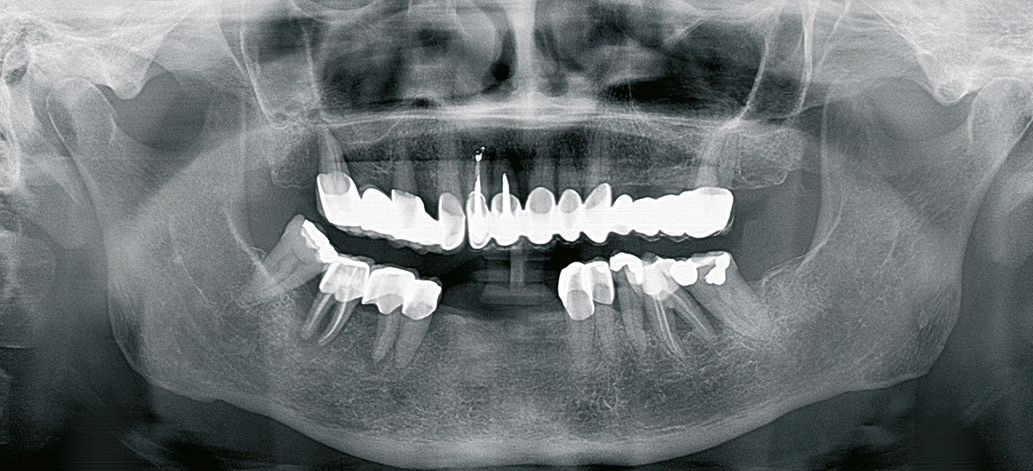

Für die Suprakonstruktionen wurde das Sekundärgerüst auf Abutment-Niveau gefräst. Der Patient bekam im Oberkiefer ein System mit interner Sechskantverbindung (Abb. 9-16). Die Patientin im Unterkiefer bekam ein System desselben Herstellers mit konischer Abutmentverbindung (Abb. 1-8). Davon ist ein Implantat noch in der Einheilphase verloren gegangen. Der betroffene Kiefer konnte trotzdem mit fünf Implantaten versorgt werden. Vom Prinzip „all-on-4“ wurde bewusst Abstand genommen. Ebenso wurde auch auf geneigt gesetzte Implantate verzichtet. Die Implantate, die abgewinkelte Abutments bekamen, wurden nach den prothetisch und anatomisch günstigsten Knochenverhältnissen gesetzt.